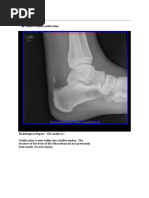

Reason for Study Rolled ankle on 6th of July while travelling in Europe dx with metatarsal fracture now home in plaster cast.

Imaging obtained through casting material. Undisplaced base of fifth metatarsal fracture with persistent lucent

fracture line visible. Faint periostitis suspected but no significant bridging callus. No other significant bone or

joint abnormality.